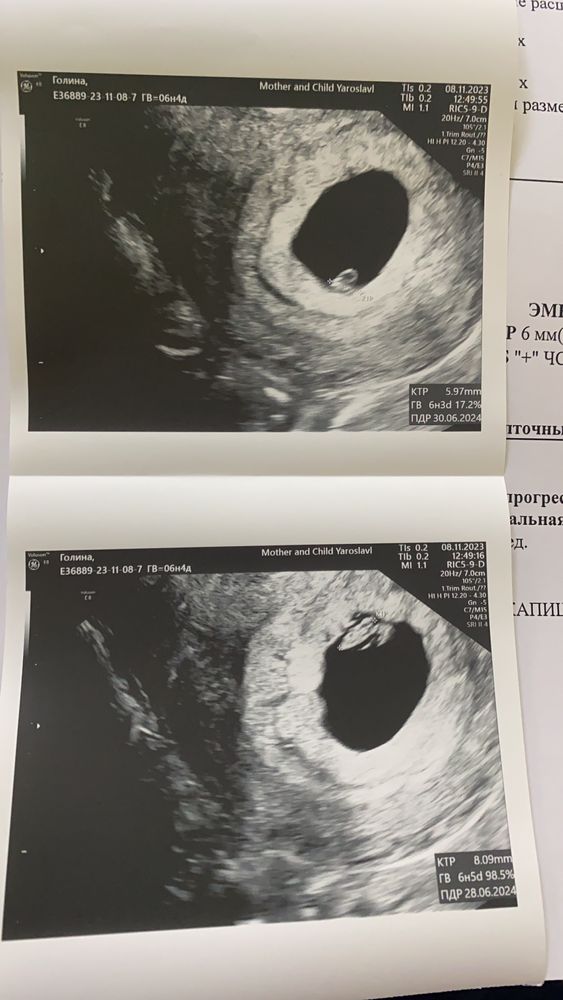

Таня, Изображение Изображение

Юлия, теперь я поняла, что этот черный овал в центре (с 2мя эмбриончиками) -это не матка, это и есть плодное яйцо 🙈😅 а матка - серая толстая вокруг. Спасибо, что помогли разобраться 🙏🏻